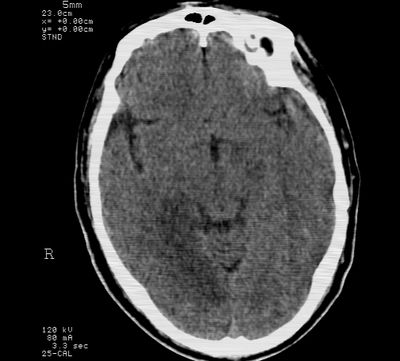

标题: CT21793:李x,男,62岁,头疼,头晕,家属否认有出血病史, [打印本页]

标题: CT21793:李x,男,62岁,头疼,头晕,家属否认有出血病史,

右枕叶.右侧脑室前角旁脑梗塞

右基底节,海马并侵及右枕,左枕叶梗塞

右枕叶.右侧脑室前角旁脑梗塞。

支持多发脑梗塞

支持右基底节,海马并侵及右枕,左枕叶梗塞。

支持右基底节,海马并侵及右枕,左枕叶梗塞。建议增强。

支持右基底节,海马并侵及右枕,左枕叶梗塞

多发性梗塞

多发梗塞,左小脑软化灶

支持多发脑梗塞!

多发性脑梗塞。

考虑多发脑梗塞,建议mri检查。